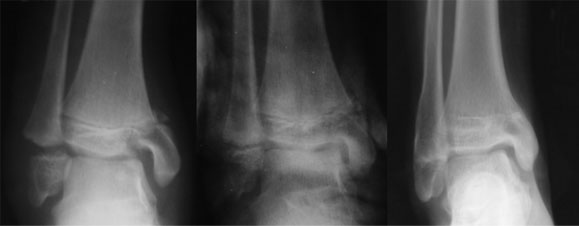

The xray picture shows one of the most common causes of deformity i.e. injury to the epiphysis(growth plate). As the growth plate heals it fuses and the growth arrests causing deformity.

There are various other causes of sectoral or complete growth arrests e.g. congenital or develeopmental growth plate defects, infection, hormonal imbalance etc.